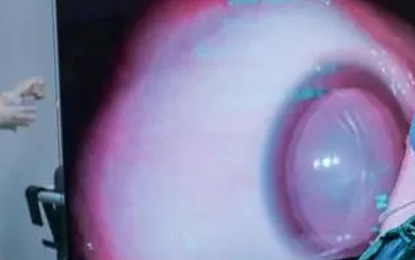

年轻时我们的晶体是全自动变焦镜头,远近物都看得很清楚;随着年龄增大、机体衰老,晶体的透明度就会降低或者颜色发生改变,致使晶体变得浑浊,导致白内障。

可以通过手术治疗,白内障术后需要植入人工晶体。目前有多种晶体可供选择:单焦点、双焦点、多焦点。

患者可以分别选择不同焦点晶体提高视力,实现远景、中景、近景均能“清晰可见”的需求,极大提高老年患者的生活质量,脱掉眼镜,无需戴远视、近视及老花眼镜。